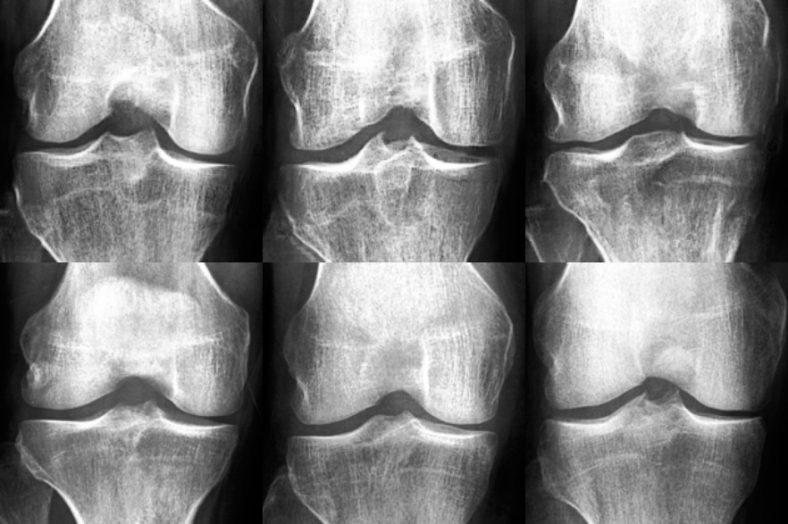

AI-generated x-ray images fooled medical experts and improved osteoarthritis classification

Sharing medical data between laboratories and medical experts is important for medical research. However, data sharing is often sufficiently complex ...